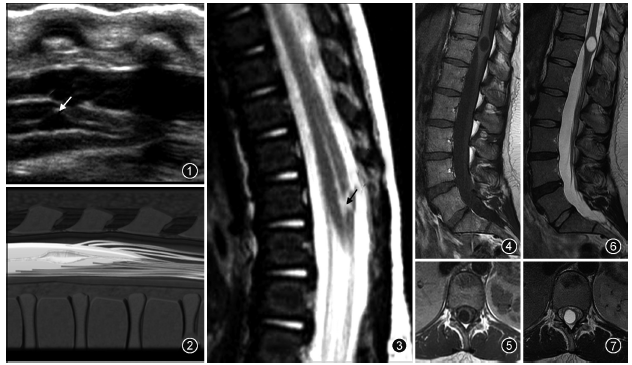

超声是诊断胎儿或新生儿第五脑室的一种常用检查方法(图1~3)。第五脑室在超声矢状切面图上显示为脊髓圆锥区域囊状扩张的低回声区并可与中央管相通,在超声横断切面图上表现为扩张的低回声囊腔且与周围脊髓组织有着较为清楚的分界。MR检查为诊断第五脑室的主要手段。第五脑室在MRI上通常表现为脊髓圆锥内边缘清楚的卵圆形囊腔,形态规则,囊壁光整,且与周围正常的脊髓组织分界清楚,囊内为T1WI低(图4,5)、T2WI(图6,7)高的脑脊液信号,囊内分隔及囊周水肿

性改变比较少见,增强扫描后囊壁不强化。

图1~3 男,5 d。超声矢状切面显示第五脑室是位于脊髓圆锥内且囊壁光滑的囊腔(图1,↑);图2为图1的示意图;矢状面T2WI显示第五脑室是位于脊髓圆锥中央的囊性扩张结构,囊内呈高信号(图3,↑) 图4~7 男,45岁。腰椎MRI显示第五脑室是位于脊髓圆锥内且囊壁光滑的囊腔,囊腔内的脑脊液在矢状面T1WI上呈低信号(图4),在横断面T1WI上呈低信号(图5),在矢状面T2WI上呈高信号(图6),在横断面T2WI上呈高信号(图7)。所有图片均由加拿大渥太华大学渥太华医院Carlos Torres教授提供